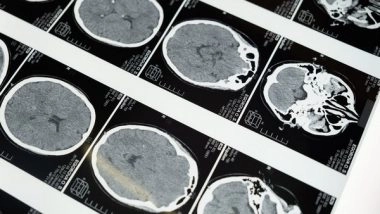

Washington [US], May 10 (ANI): The findings from a seven-year research project suggests that there could be a new approach to treating one of the most common and devastating forms of brain cancer in adults, Glioblastoma Multiforme (GBM).

In a peer-reviewed study published by BMC Cancer, scientists from the University of Surrey show that a short chain of amino acids (the HTL-001 peptide) is effective at targeting and inhibiting the function of a family of genes responsible for the growth of GBM - Hox genes. The study was conducted in cell and animal models.